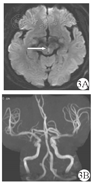

例3男,68岁,既往有高血压及2型糖尿病病史,平素未服用药物,未系统监测血压及血糖。患者因"头晕1 d,复视12 h"入院。患者1 d前无明显诱因出现头晕,视物旋转,行走不稳;伴恶心,无呕吐,无视物不清,无肢体麻木无力等不适,未诊治,症状持续存在。12 h前患者突然出现复视,头晕仍持续不缓解,遂就诊于我院。入院查体:意识清楚,言语流利。GEN阳性,水平头脉冲试验向右侧阳性。双侧面纹对称,伸舌居中,四肢肌力肌张力正常,双侧病理征阴性,深浅感觉无异常。入院当天行头颅磁共振示脑干梗死(图3)。入院后给予口服阿司匹林肠溶片(100 mg/次,1次/d)、氢氯吡格雷(75 mg/次,1次/d)抗血小板聚集、阿托伐他汀钙(20 mg/次,1次/d)调节血脂,并给予相应对症支持处理,病情好转后出院。

注:3A:DWI示内侧纵束高信号,提示内侧纵束急性梗死;3B:脑血管成像未见明显异常